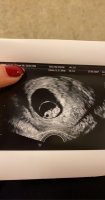

Jeg var ca 5+6 første gangen når hun så bare plommesekken. I dag skal jeg være ca 6+6, hun målte ca 6+4 som hun sa var bra. Og at jeg muligens er ca 6+4/6+5, men kan også være 6+6. Utstyrer er ikke tipp topp, men helt greit.Så deilig utfall

Så ett lite hjerte banke og er så glad for det

. Viste seg å være noen dager bak forventet dato. Så vi bestemte oss for å ikke ta mer blodprøver, heller ny ul neste uke. Og være positive og glede seg over et lite hjerte som banker i magen min